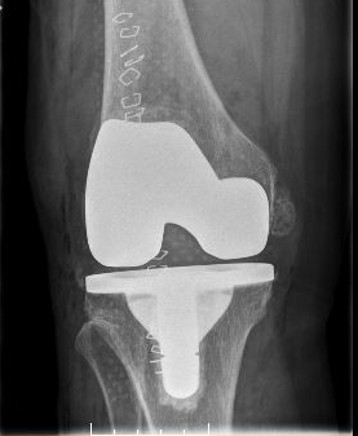

Example X-Ray Images

Knee Replacement

A surgical procedure performed to replace worn joint surfaces in the knee, usually due to severe arthritis. An incision is made on the front of the knee and the worn joint surfaces are removed. Metal components are then cemented on the tibia and femur. A spacer made of a specialized plastic is placed in between the tibia and femur. The surface of the knee cap is also removed and replaced with a plastic button. When all of the components are in place the knee is checked to ensure appropriate range of motion, alignment, and stability.

A total knee replacement is a replacement of the three compartments of the knee (patellofemoral, medial, and lateral) with metal and a plastic spacer in between. There are three components to the replacement – a metal end of the femur and tibia, and a polyethylene spacer.

What are knee replacements made of?

Knee replacements are made of metal alloy such as cobalt chromium. The spacers in between the metal components are made of polyethylene.